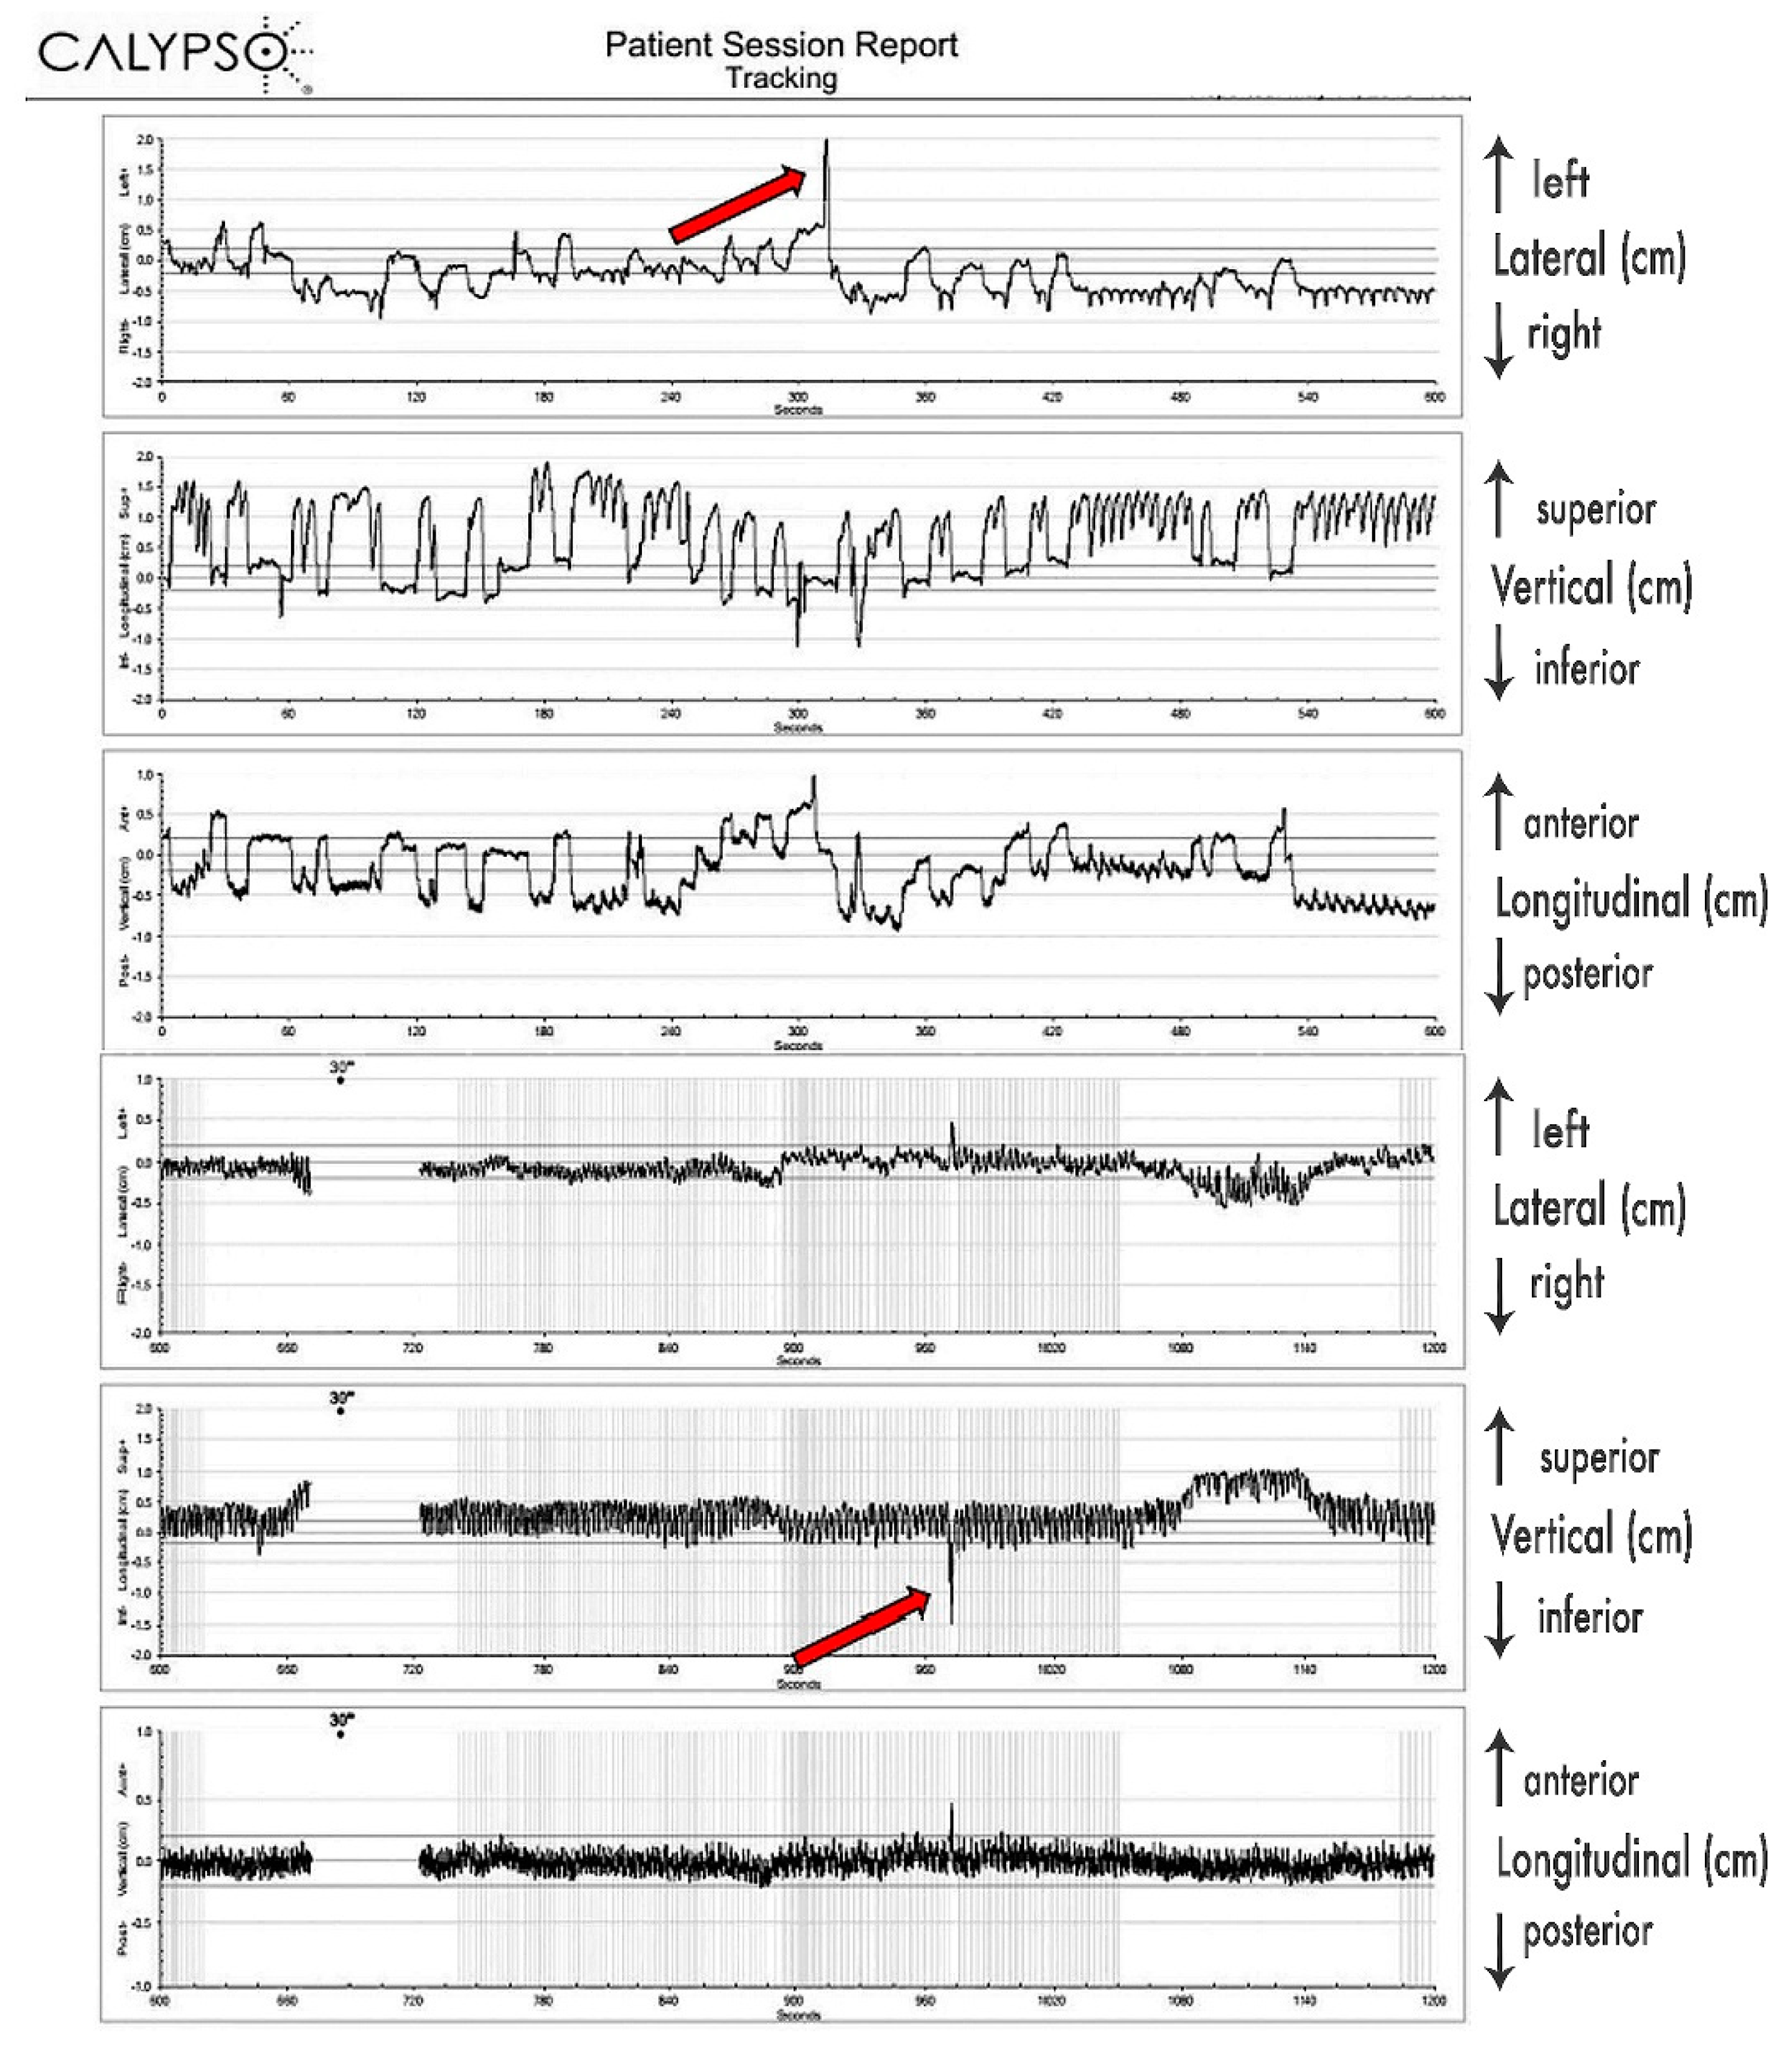

Since 4D-CT by default records predominantly respiratory-induced movements, these differences were most probably caused by additional movements of the pancreatic tumor, most likely caused by peristalsis, heartbeat, changes of the breathing patterns (frequency, amplitude), stomach and intestine filling, drift, and possibly some other, yet undetermined causes. Their contributions seem to be significant. As presented in

Figure 3, those additional tumor movements appear to be non-periodical, as well as being unrelated to respiratory movements, and their time share in overall tumor excursions remains to be further investigated, probably in its own study. As we determined the full extent of pancreatic tumor excursions only in free breathing, further investigation on the extent of those excursions should be conducted during motion mitigation and deep breath hold.